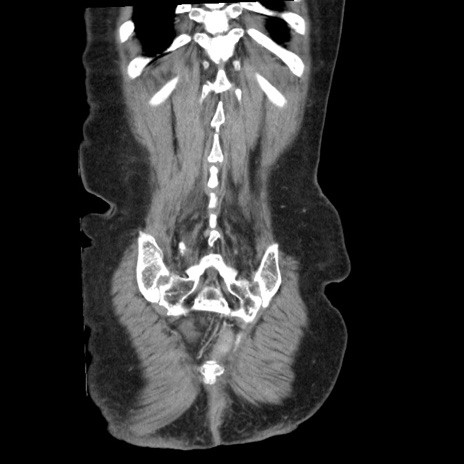

症例1(冠状断像)

【症例】80歳代女性

【主訴】腹痛

【現病歴】8時間前から腹痛あり来院。

【既往歴】糖尿病、脂質異常症、子宮体癌にて子宮全摘術

【身体所見】意識清明・会話良好だが腹痛で苦悶様、全腹部にわたって反跳痛と圧痛あり

【データ】WBC 13600、CRP 0.14、LDH 224、CK 90